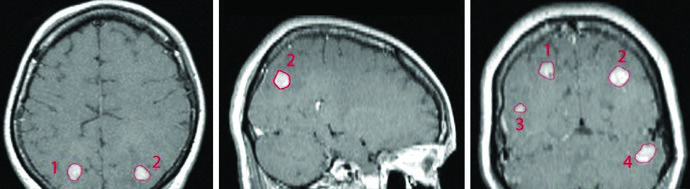

A SRS de múltiplos isocentros permite tratar simultaneamente lesões em diferentes localizações — como nos lobos parietais, temporal e cerebelo — em uma única sessão de tratamento. No exemplo do livro, quatro metástases de câncer de mama (volumes de 0,07 a 1,92 cm³, diâmetros de 6 a 20 mm) foram tratadas com fração única em paciente que já recebera WBRT prévia de 30 Gy em 10 frações. O GTV de cada lesão foi definido pela captação de contraste na RM T1 pós-gadolínio, e com Gamma Knife, PTV e CTV utilizaram expansão de 0 mm a partir do GTV.